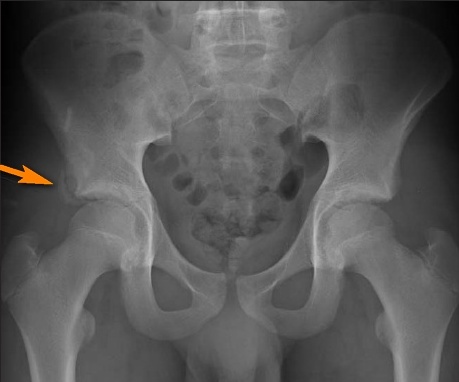

Травмы бывают разные от ушибов до переломов поскольку большинство травм мы получаем в юношестве они являются самыми опасными в это время нас не заботит как они отразятся на нашем состоянии потом, через много лет. А зря, например мальчик, играя во дворе упал и ушиб ягодицу. Пришёл домой и вроде ничего, но она начинает сильно болеть и ломить мальчик просит родителей посмотреть что это может быть соответственно Мама, и Папа повезли его на приём к травматологу. Диагноз-трещина тазовой кости. Накладывают гипс, мальчик лежит в больнице. Он выздоравливает как по часам, но напутствие врача не должно остаться неуслышанным. "мальчик, ты должен быть аккуратным, у тебя очень серьёзная травма. Воздержись от падений. В очень нескором будущем, она будет тебе напоминать, о том, что нельзя быть таким невнимательным и рассеянным. Тем временем мальчик повзрослел и уже его организм, помимо детской травмы, перенес не малое количество ушибав переломов и трещин. Поскольку молодого человека это не заботит, он продолжает небрежно относится к своему здоровью, не думая о последствиях. Будучи пожилым человеком, его больные суставы и кости, будут ему напоминать на сколько он был невнимателен даже имея такую продвинутую медицину в наше время нельзя избавится от боли которую мы заработали в юношестве.